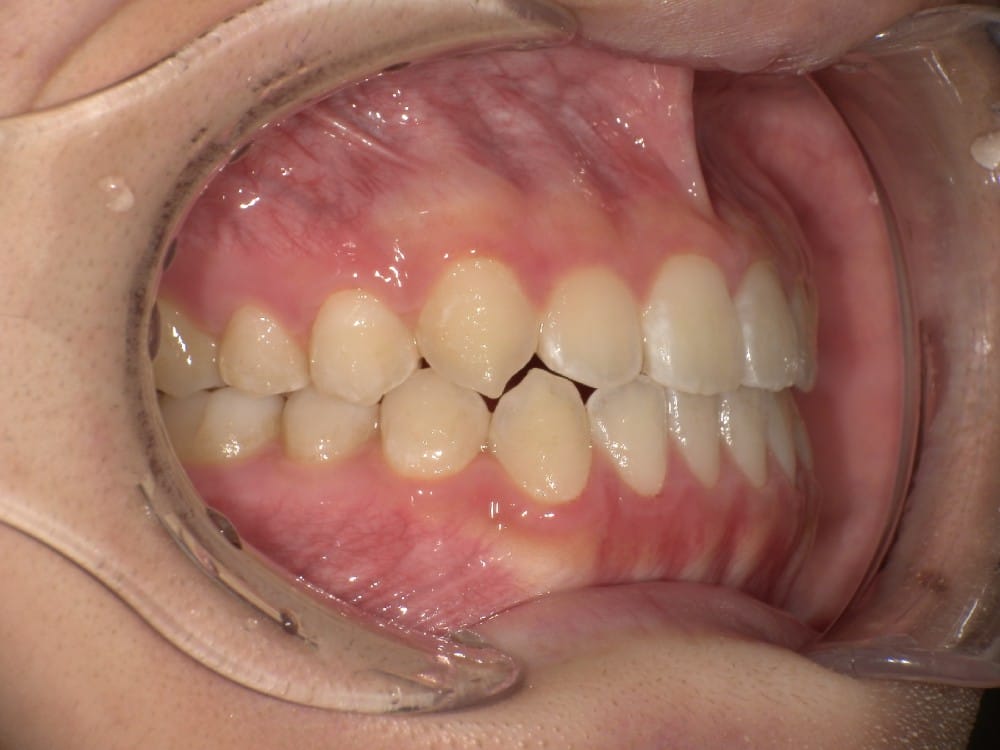

この子は、中学生の女の子で、受け口、横顔が気になるとのことでご来院されました。

治療前の様子

分析をしますと

- 骨格的な上下あごの前後差は中等度

- 噛み合わせの位置も下あごの奥歯が半分くらい前にズレていた

- 上の前歯が前に傾斜、下の前歯が内側に傾斜しているにもかかわらず、受け口

というケースで、外科的な処置も検討するようなケースでした。

患者さまに外科的な手術の選択肢も提示しましたが、希望されず、横顔の変化はおそらく起こらないことを納得の上、治療をスタートいたしました。